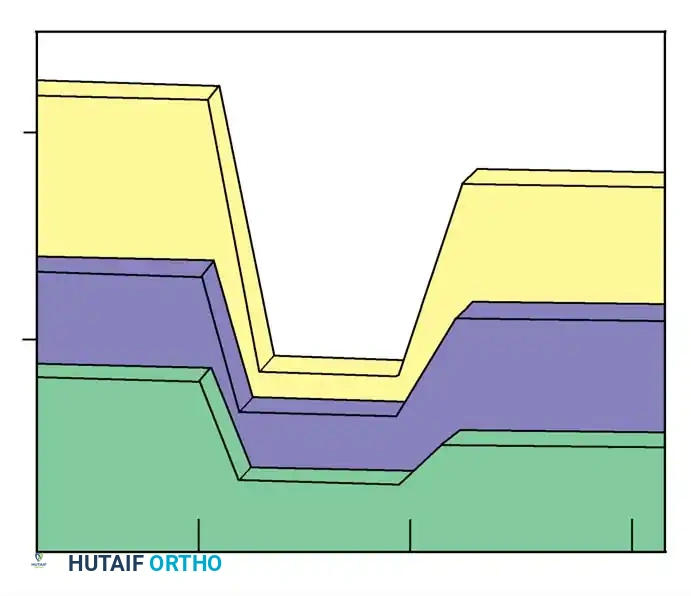

Evaluation of Brace Treatment of Juvenile Idiopathic Scoliosis by the RVAD:

* If the RVAD progresses above 10 degrees during brace wear, curve progression is highly expected.

* If the RVAD values decline as treatment continues, transitioning to part-time Milwaukee brace wear is generally adequate.

* Curves presenting with RVAD values near or below 0 degrees at the time of diagnosis typically require only a short duration of full-time brace wear before part-time wear can be safely initiated.

Kahanovitz, Levine, and Lardone demonstrated that patients with curves less than 35 degrees and RVADs less than 20 degrees exhibited excellent prognoses with a part-time Milwaukee brace program. Conversely, patients with curvatures exceeding 45 degrees at the onset of bracing, coupled with RVADs greater than 20 degrees, universally failed conservative management and required spinal fusion.